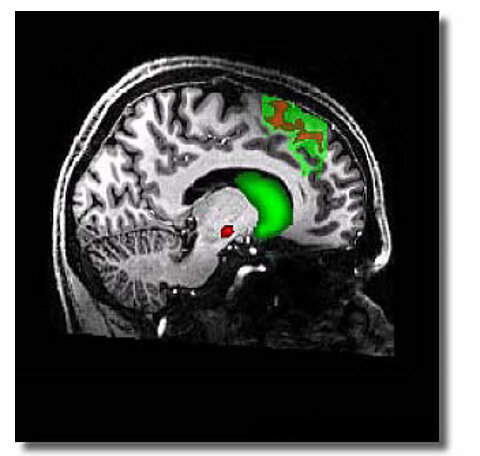

Изображение, полученное с томографа, демонстрирует связь между ДМО (дополнительной моторной областью коры головного мозга) и полосатым телом (striatum). Они обозначены зеленым цветом. Чем более связаны эти участки мозга, тем более рационально человек реагирует на событие в ситуации недостатка времени.

Нейробиологи из Великобритании, Германии, Австралии и Нидерландов под руководством Бирта Фортсмана (университет Амстердама) провели серию экспериментов. Для начала они отобрали несколько здоровых, обладающих хорошим зрением, праворуких добровольцев. Таким образом были значительно нивелированы различия в работе мозга, не связанные с условием проведения экспериментов.

Эксперимент выявил четкую зависимость между временем и качеством ответом — чем быстрее отвечал человек, тем чаще он ошибался, и наоборот. Более важным стало выявить особенности работы головного мозга. Для этого осуществлялось сканирование мозга магнитно-резонансным томографом.

В результате оказалось, что

предрасположенность к осторожности или риску зависит от качества связей между корой головного мозга и полосатым телом. Выяснилось, что основной вклад вносит связь с дополнительной моторной областью коры — ДМО. Согласно ранее полученным данным, ДМО участвует в планировании движений.

Математический анализ позволил сделать выводы, что индивидуальные особенности каждого человека в скорости принятия решений зависят от прочности связей между полосатым телом и дополнительной моторной областью коры головного мозга.

Чем надежнее связаны эти участки мозга, тем более рационально человек способен оценивать ситуацию и выбирать оптимальный компромисс между скоростью мышления и его качеством.